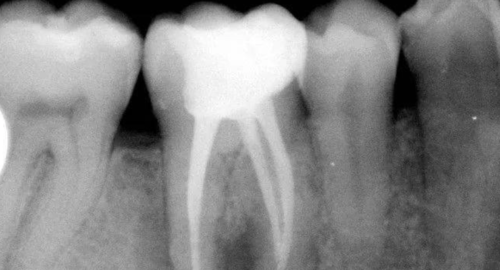

A:口内(左上)和X线片(左下)见15残根,需拔除,右图为示意图;B:通过涡轮钻切割(左),挺除远中部分牙根(中)后,形成远中(凹面)低点的断面(右);C:在近中插入分离器械;D:牙根转动脱位;E:达成微创拔除的效果;F:拔除的牙根可见切割形成的断面。